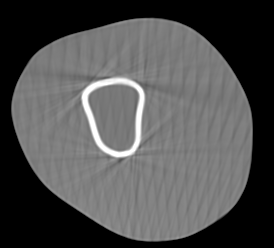

Involuntary subject motion is the main source of artifacts in weight-bearing cone-beam CT of the knee. To achieve image quality for clinical diagnosis, the motion needs to be compensated. We propose to use inertial measurement units (IMUs) attached to the leg for motion estimation. We perform a simulation study using real motion recorded with an optical tracking system. Three IMU-based correction approaches are evaluated, namely rigid motion correction, non-rigid 2D projection deformation and non-rigid 3D dynamic reconstruction. We present an initialization process based on the system geometry. With an IMU noise simulation, we investigate the applicability of the proposed methods in real applications. All proposed IMU-based approaches correct motion at least as good as a state-of-the-art marker-based approach. The structural similarity index and the root mean squared error between motion-free and motion corrected volumes are improved by 24-35% and 78-85%, respectively, compared with the uncorrected case. The noise analysis shows that the noise levels of commercially available IMUs need to be improved by a factor of $10^5$ which is currently only achieved by specialized hardware not robust enough for the application. The presented study confirms the feasibility of this novel approach and defines improvements necessary for a real application.